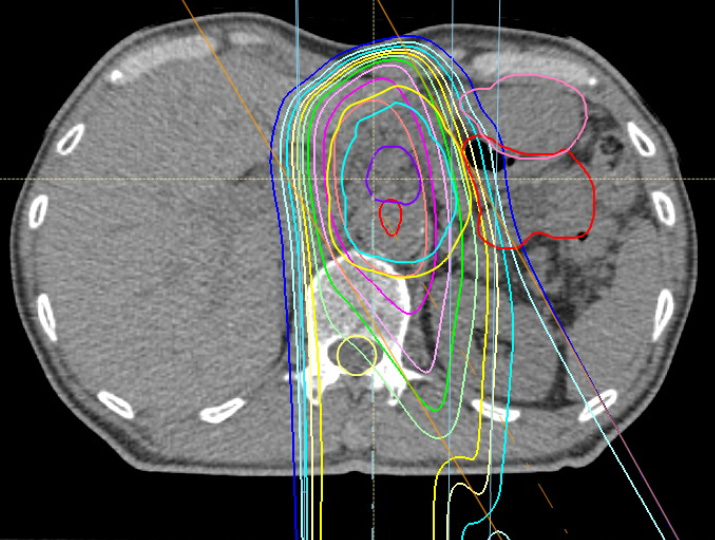

実際の線量分布の例を下に示します。水色の線が病変の範囲、内側のオレンジの線が67.5 Gy(RBE)の95%(64.1 Gy(RBE))が照射されている範囲。右方の赤やピンクの線が胃腸です。